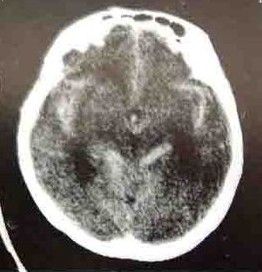

自發性蛛網膜下腔出血CT圖動脈瘤為最常見的出血原因大宗文獻統計表明動脈瘤出血占蛛網膜下腔出血病人的52%。此外,尚有一部分查不清死因者,其所占的比例受診斷條件影響,過去曾高達46.3%。隨著檢查手段的進步,對蛛網膜下腔出血的病因檢出率增加,不明原因的比例下降為9%~20%。血液病、顱內感染、藥物中毒等造成蛛網膜下腔出血者也偶見。

自發性蛛網膜下腔出血CT圖數蛛網膜下腔出血病例與吸菸有關,並呈量效依賴關係。經常吸菸者發生蛛網膜下腔出血的危險係數是不吸菸者的11.1倍男性吸菸者發病可能性更大。吸菸後的3h內是最易發生蛛網膜下腔出血的時段。酗酒也是蛛網膜下腔出血的好發因素,也呈量效依賴關係,再出血和血管痙攣的發生率明顯增高,並影響蛛網膜下腔出血的預後擬交感類物使用者易患蛛網膜下腔出血如毒品古柯鹼可使蛛網膜下腔出血的罹患高峰年齡提前至30歲左右。

自發性蛛網膜下腔出血CT圖1.連續放液,各試管內紅細胞計數逐漸減少。